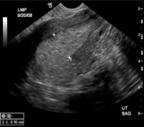

Diagnóstico

El abordaje diagnóstico inicia con la historia clínica de sangrado no asociado al coito en una mujer postmenopáusica o con factores de riesgo. Luego se realiza una ecografía transvaginal (ver imagen) donde puede verse un aumento del tamaño del endometrio más de 4mm en postmenopáusicas (más de 7mm si recibe TRH). El diagnóstico definitivo se hace mediante una biopsia guiada por histeroscopia (ver imagen) o por legrado diagnóstico. Se prefiere por histeroscopia (ENARM 2022).

Figura 25. Ecografía transvaginal Figura 26. Biopsia guiada por histeroscopia Tabla 6. Clasificación FIGO del cáncer de útero Figura 27. Lesiones del cáncer de útero